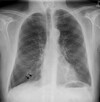

What may be seen on CXR in asbestosis?

What may be seen on CXR in bronchiectasis?

What will CXR show in mycoplasma pneumonia?